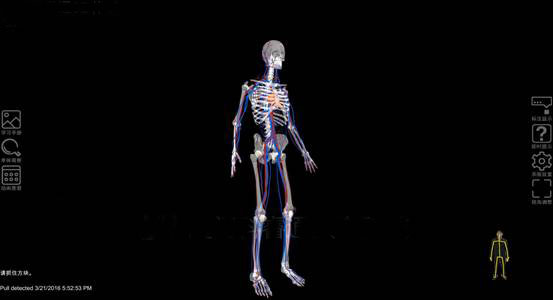

增強現(xiàn)實(Augmented Reality,AR)技(jì)術(shù)是(shì)一( yī)種将虛拟信息與真實世界巧妙融合的(de)技(jì)術(shù),廣泛運用(yòng)了(le)多(duō)媒體(tǐ)、三維建模、實時(shí)跟蹤及注冊、智能(néng)交互、傳感等多(↑duō)種技(jì)術(shù)手段,将計(jì)算(suàn)機(jī)生(shēng)成的(de)文(wén)字、圖像、三維模型、音(yīn)樂(yuè)、視(shì)頻(pín)等虛拟信息模拟仿真後,應用(yòng)到(dào)真實世界中,兩種信息互為(wè i)補充,從(cóng)而實現(xiàn)對(duì)真實世界的(de)“增強”。